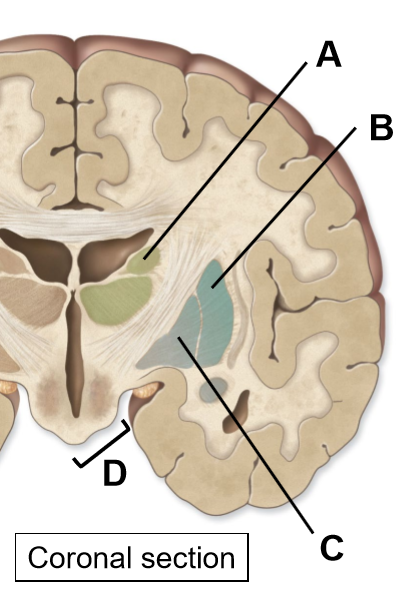

The basal nuclei includes the (4)

Caudate

Putamen

Globus pallidus/pallidum

Substantia nigra, subthalamus

A: Caudate

B: Putamen

C: Globus pallidus

D: Substantia nigra